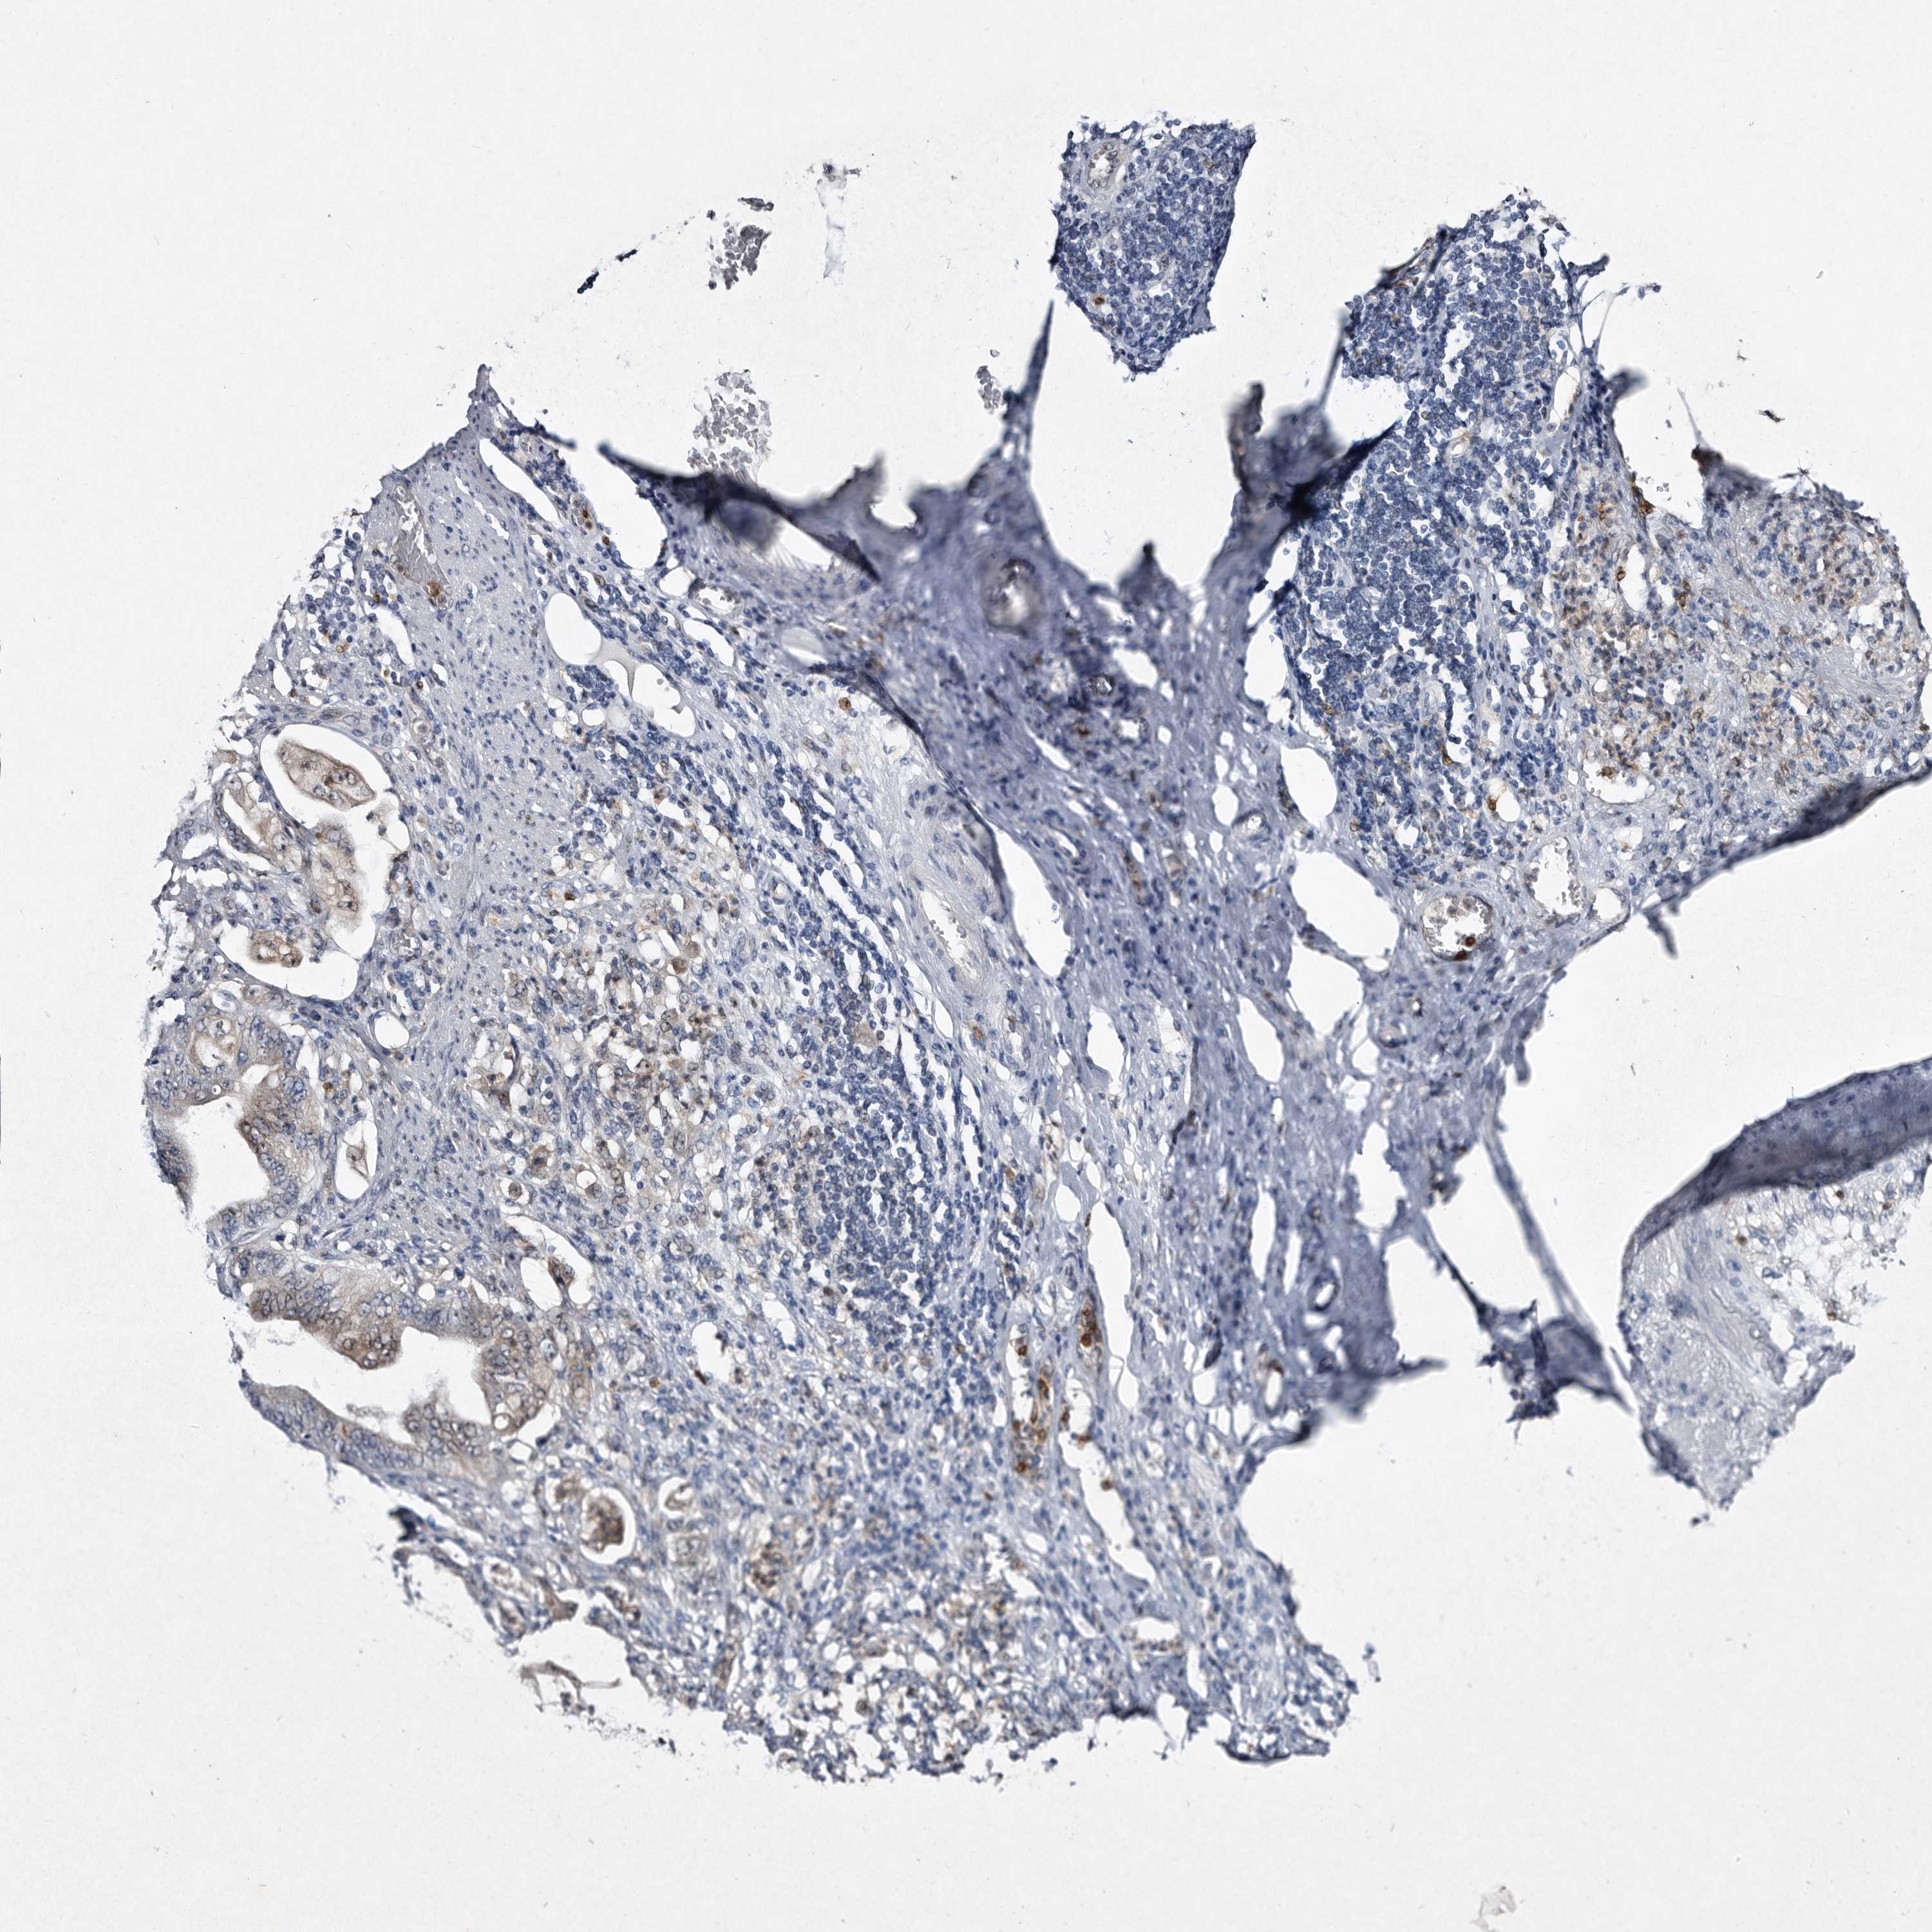

STOMACH CANCER - Protein expressioni

A mouse-over function shows sample information and annotation data. Click on an image to view it in a full screen mode. Samples can be filtered based on level of antibody staining by selecting one or several of the following categories: high, medium, low and not detected. The assay and annotation is described here.

Antibody stainingi

Antibody staining in the annotated cell types in the current human tissue is reported as not detected, low, medium, or high, based on conventional immunohistochemistry profiling in selected tissues. This score is based on the combination of the staining intensity and fraction of stained cells.

Each image is clickable and will lead to virtual microscopy that enables deeper exploration of all samples and also displays staining intensity scores, fraction scores and subcellular localization as well as patient and tissue information for each sample.

Antibody CAB034300

Staining

High

Medium

Low

Not detected

Intensity

Strong

Moderate

Weak

Negative

Quantity

>75%

75%-25%

<25%

None

Location

Nuclear

Cytoplasmic/membranous

Cytoplasmic/membranous,nuclear

Adenocarcinoma, NOS